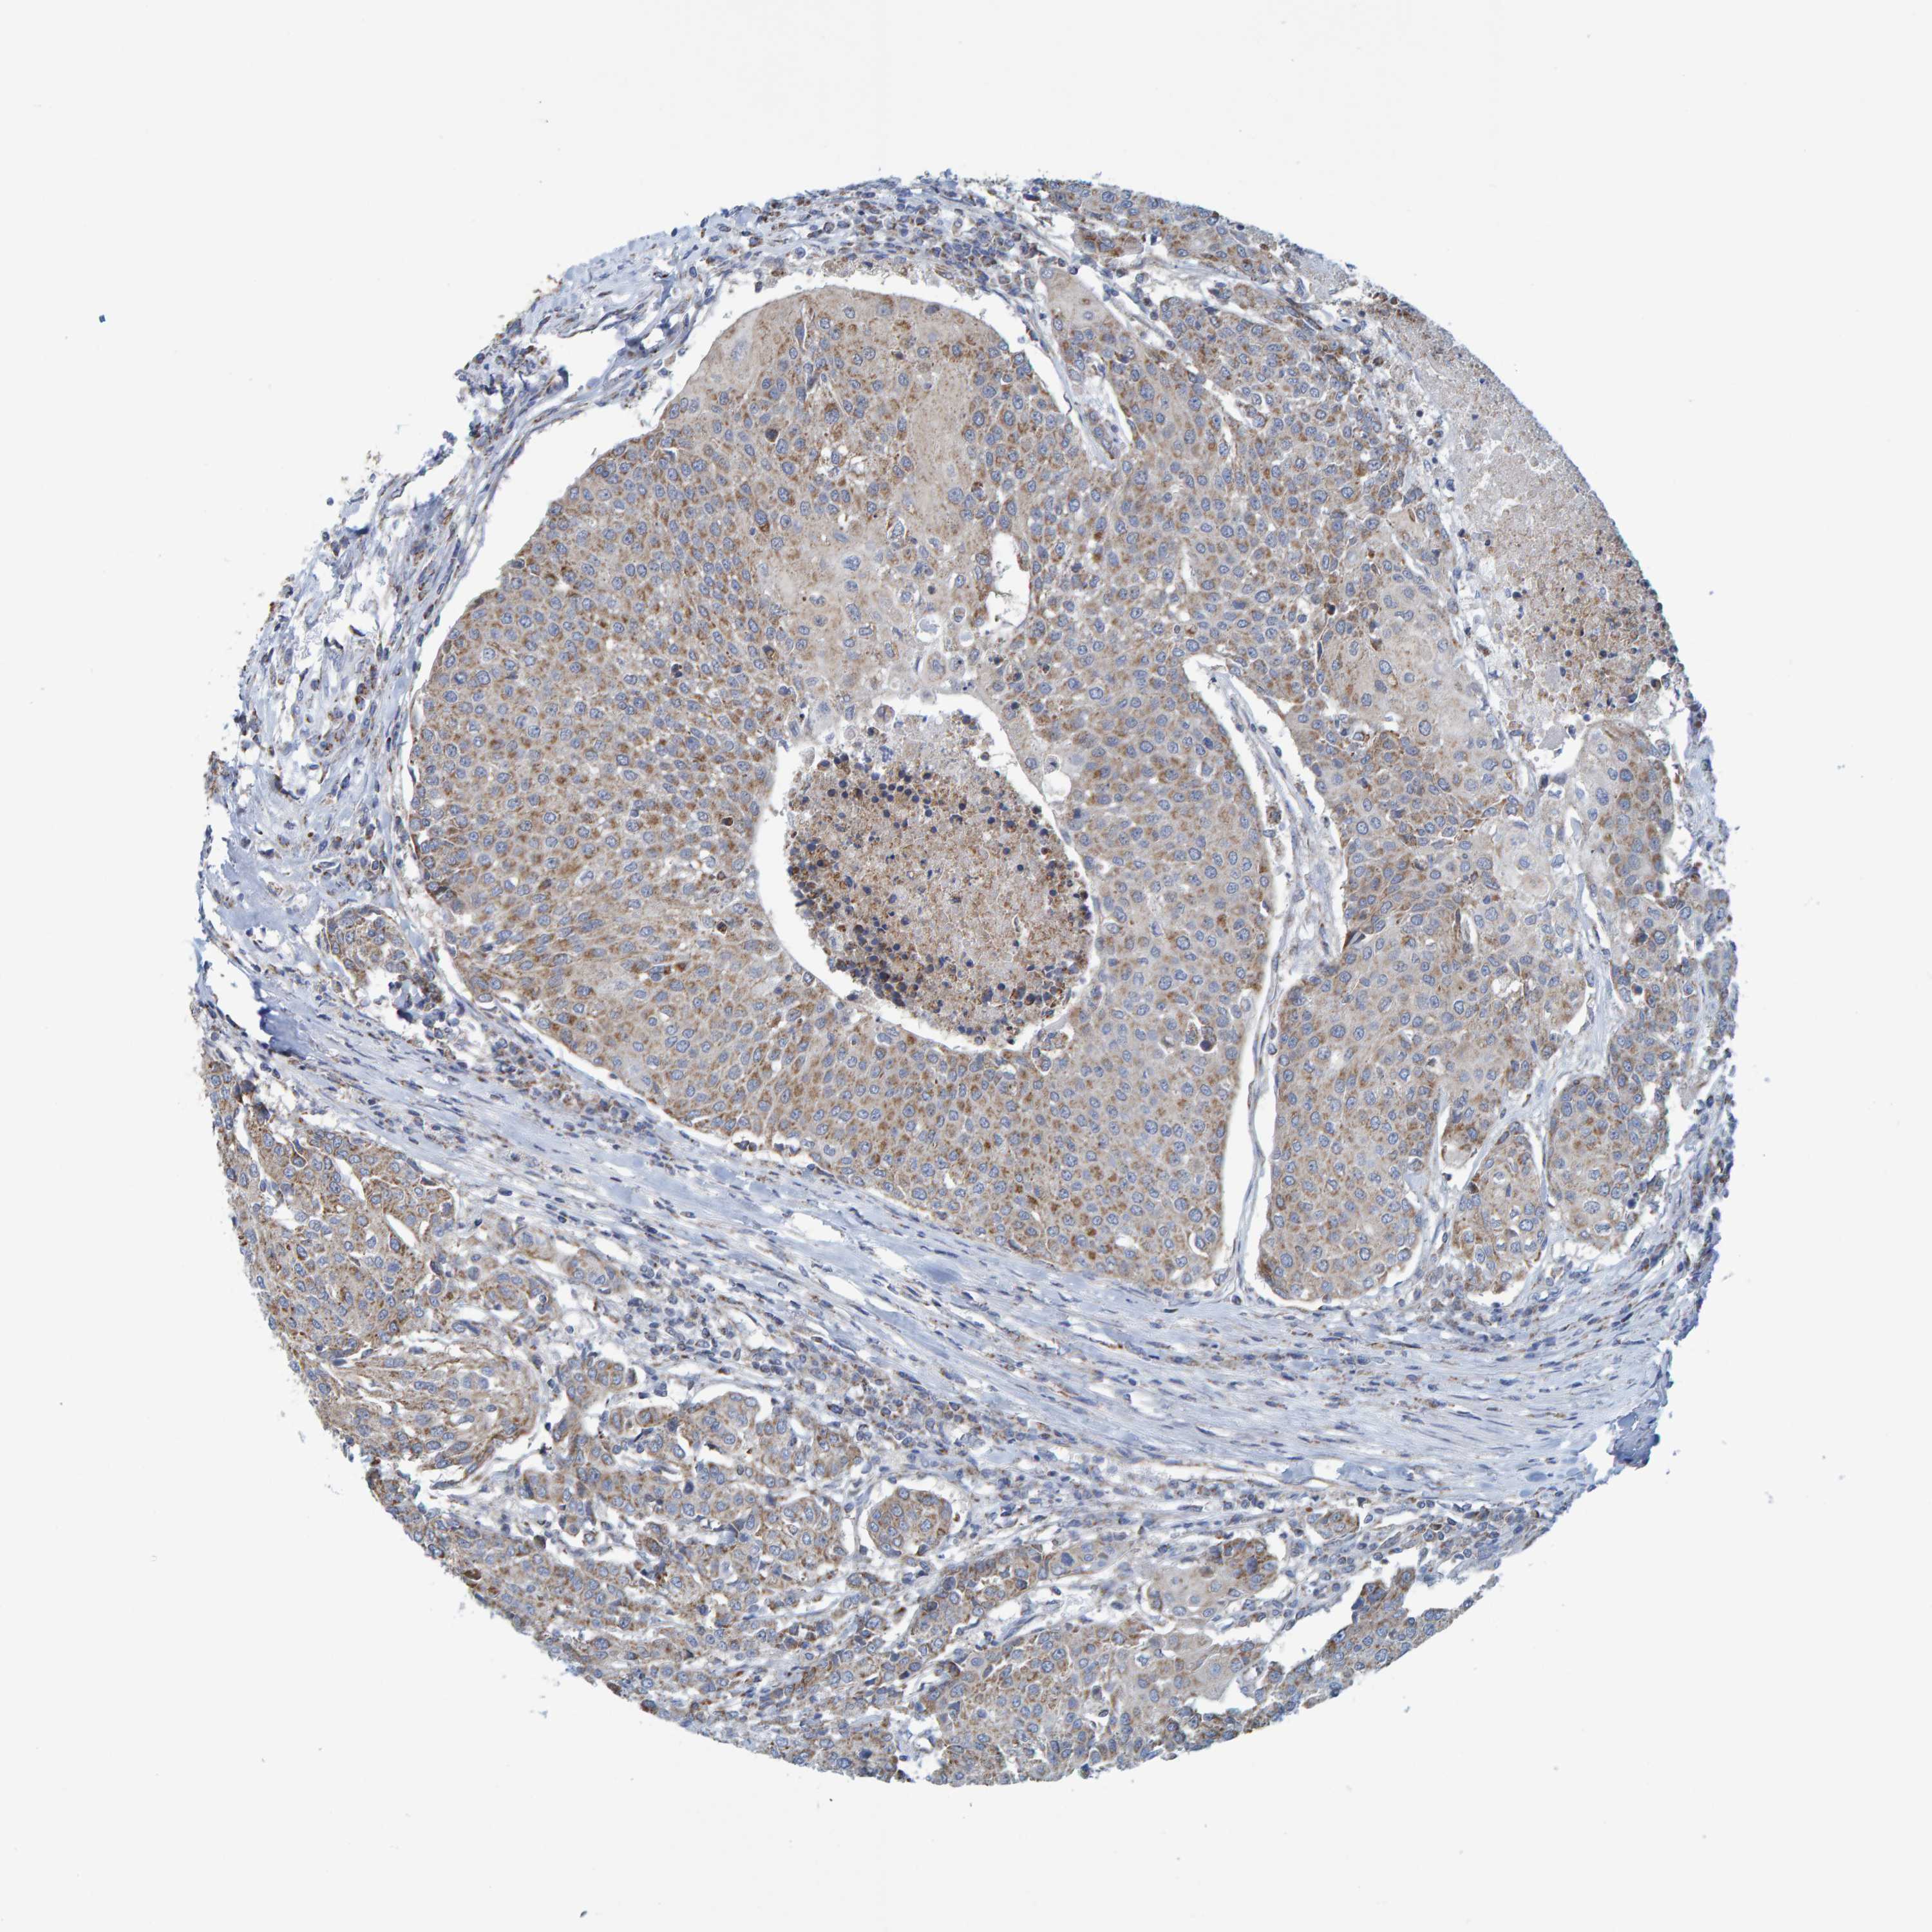

UROTHELIAL CANCER - Protein expressioni

A mouse-over function shows sample information and annotation data. Click on an image to view it in a full screen mode. Samples can be filtered based on level of antibody staining by selecting one or several of the following categories: high, medium, low and not detected. The assay and annotation is described here.

Note that samples used for immunohistochemistry by the Human Protein Atlas do not correspond to samples in the TCGA dataset.

Antibody stainingi

Antibody staining in the annotated cell types in the current human tissue is reported as not detected, low, medium, or high, based on conventional immunohistochemistry profiling in selected tissues. This score is based on the combination of the staining intensity and fraction of stained cells.

Each image is clickable and will lead to virtual microscopy that enables deeper exploration of all samples and also displays staining intensity scores, fraction scores and subcellular localization as well as patient and tissue information for each sample.

Antibody HPA022522

Antibody HPA023007

Staining

High

Medium

Low

Not detected

Intensity

Strong

Moderate

Weak

Negative

Quantity

>75%

75%-25%

<25%

None

Location

Nuclear

Cytoplasmic/membranous

Cytoplasmic/membranous,nuclear

Urothelial carcinoma, Low grade

Urothelial carcinoma, High grade